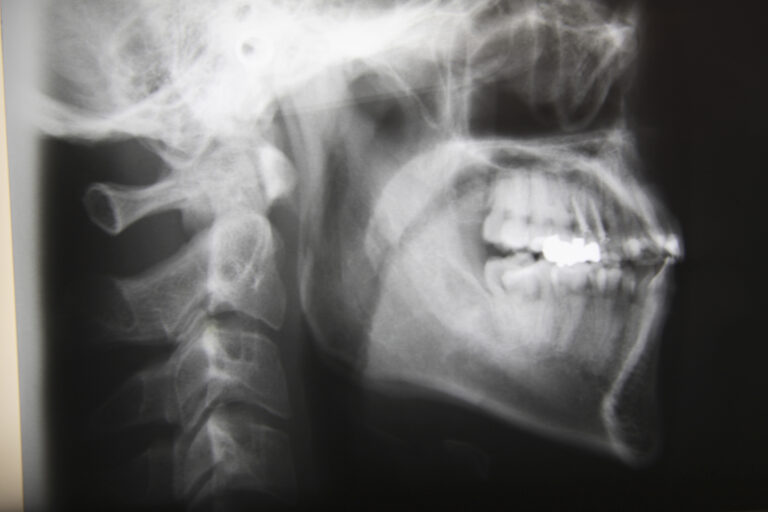

インプラント治療は、顎の骨に人工の歯根を埋め込む外科的な処置を伴う治療であるため、安全性や正確性が非常に重要になります。当院では、口腔外科分野に精通した歯科医師がインプラント治療を担当し、専門的な知識と経験をもとに、患者様一人ひとりの状態に合わせた治療を行っています。口腔外科は、歯や歯ぐきだけでなく、顎の骨、神経、血管など、お口まわりの構造を総合的に診る分野であり、インプラント治療においても、これらを正確に把握することが欠かせません。特に、顎の骨の状態が複雑な場合や、神経や血管が近接しているケース、過去に外科処置を受けた経験がある方などでは、より慎重な診断と治療計画が求められます。当院では、事前に各種検査を行い、インプラント治療が可能かどうかを丁寧に判断するとともに、治療の流れや考えられるリスクについても分かりやすくご説明します。また、持病をお持ちの方や全身状態に配慮が必要な方についても、状況を確認しながら無理のない治療計画を検討します。すべての方に同じ治療を行うのではなく、安全性と長期的な安定を重視したインプラント治療を心がけている点が当院の特徴です。外科処置に不安を感じている方や、インプラント治療について詳しく知りたい方も、まずは安心してご相談ください。

日本口腔外科専門医とは、日本口腔外科学会が定める厳格な基準を満たし、口腔外科分野において高度な知識と経験を有すると認定された歯科医師のことを指します。口腔外科は、歯や歯ぐきの治療にとどまらず、顎の骨、口腔内の粘膜、神経、血管、顎関節など、お口まわり全体を対象とする専門分野であり、外科的処置を含む幅広い診療に対応することが求められます。日本口腔外科専門医の認定を受けるためには、一定年数以上の臨床経験を積み、多くの症例を経験したうえで、学会が定める研修や試験に合格する必要があります。また、専門医資格は一度取得すれば終わりではなく、継続的な研鑽や学術活動を通じて、最新の知識と技術を維持していることが求められています。そのため、日本口腔外科専門医は、外科的な判断力や安全管理に関する知識、全身状態を考慮した治療計画の立案などにおいて、専門性の高い視点を持っているとされています。インプラント治療においても、顎の骨の状態や神経・血管の位置を正確に把握し、リスクを考慮したうえで治療を進めることが重要であり、口腔外科分野に精通した歯科医師が担当することで、より慎重で的確な判断が期待できます。ただし、専門医であってもすべての治療が必ず成功するというものではなく、患者様一人ひとりの状態に合わせた診断と十分な説明が欠かせません。日本口腔外科専門医とは、専門的な知識と経験を背景に、安全性と適切な治療を重視する歯科医師であり、外科的処置に不安を感じている方にとって、一つの安心材料となる存在といえるでしょう。